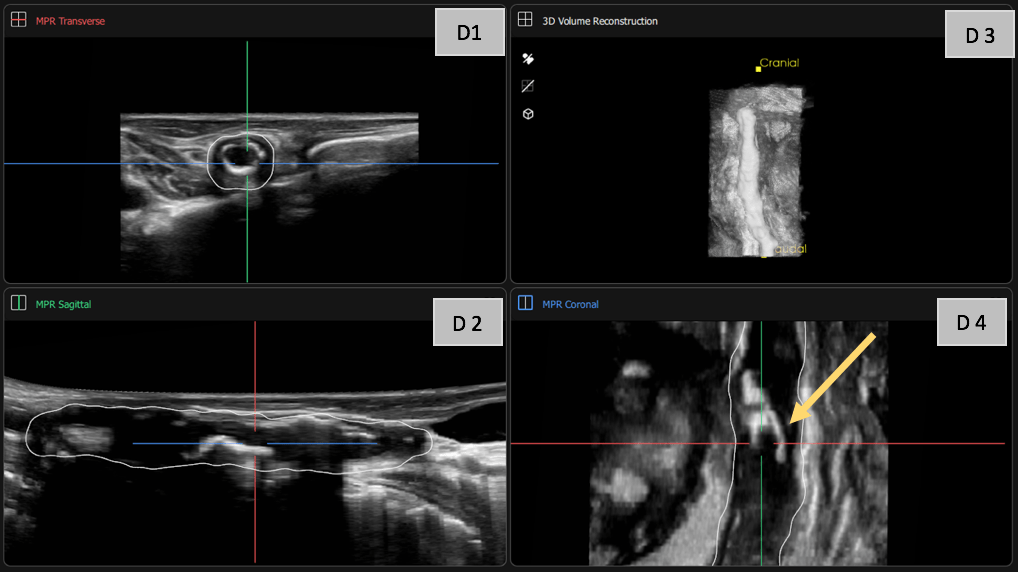

D: Visualization of the vessel with the PIUR tUS Infinity v4.1.2 General Imaging App in the transverse plane (D1), reconstructed sagittal plane (D2), and reconstructed coronal plane (D4). The coronal plane particularly highlights the vessel narrowing caused by the plaques (yellow arrow). The additional 3D reconstruction (D3) provides an "external" view of the multiple plaques, illustrating the resulting irregular vessel morphology.

• Enhanced Understanding with 3D Ultrasound: Three-dimensional (3D) ultrasound provides a unique perspective by offering tomographic imaging of vascular anatomy. This modality enables superior spatial visualization of complex plaque morphology and vessel wall structures, aiding in identifying subtle irregularities and refining risk assessment.